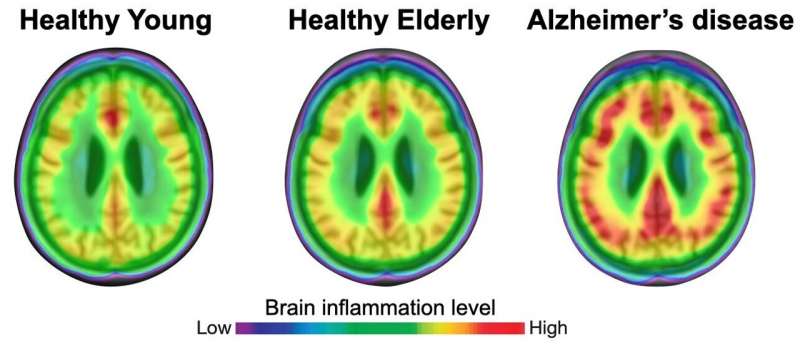

(Alzheimer-Immagine: sia i giovani che gli anziani hanno un grado di neuroinfiammazione (rosso) inferiore rispetto ai pazienti con malattia di Alzheimer. Credito: adattato da Pascoal et al., Nature).

I ricercatori hanno scoperto che la neuroinfiammazione era più diffusa nelle persone anziane e che era ancora più pronunciata nei pazienti con lievi disturbi cognitivi e in quelli con demenza associata al morbo di Alzheimer. L’analisi bioinformatica ha confermato che la propagazione della tau dipendeva dall’attivazione della microglia: è un elemento chiave che collega gli effetti dell’aggregazione della placca amiloide alla diffusione della tau e, in definitiva, al deterioramento cognitivo e alla demenza.

“Molte persone anziane hanno placche amiloidi nel cervello, ma non sviluppano mai l’Alzheimer”, ha detto Pascoal. “Sappiamo che l’accumulo di amiloide da solo non è sufficiente a causare la demenza: i nostri risultati suggeriscono che è l’interazione tra neuroinfiammazione e patologia amiloide che scatena la propagazione della tau e alla fine porta a danni cerebrali diffusi e deterioramento cognitivo“.